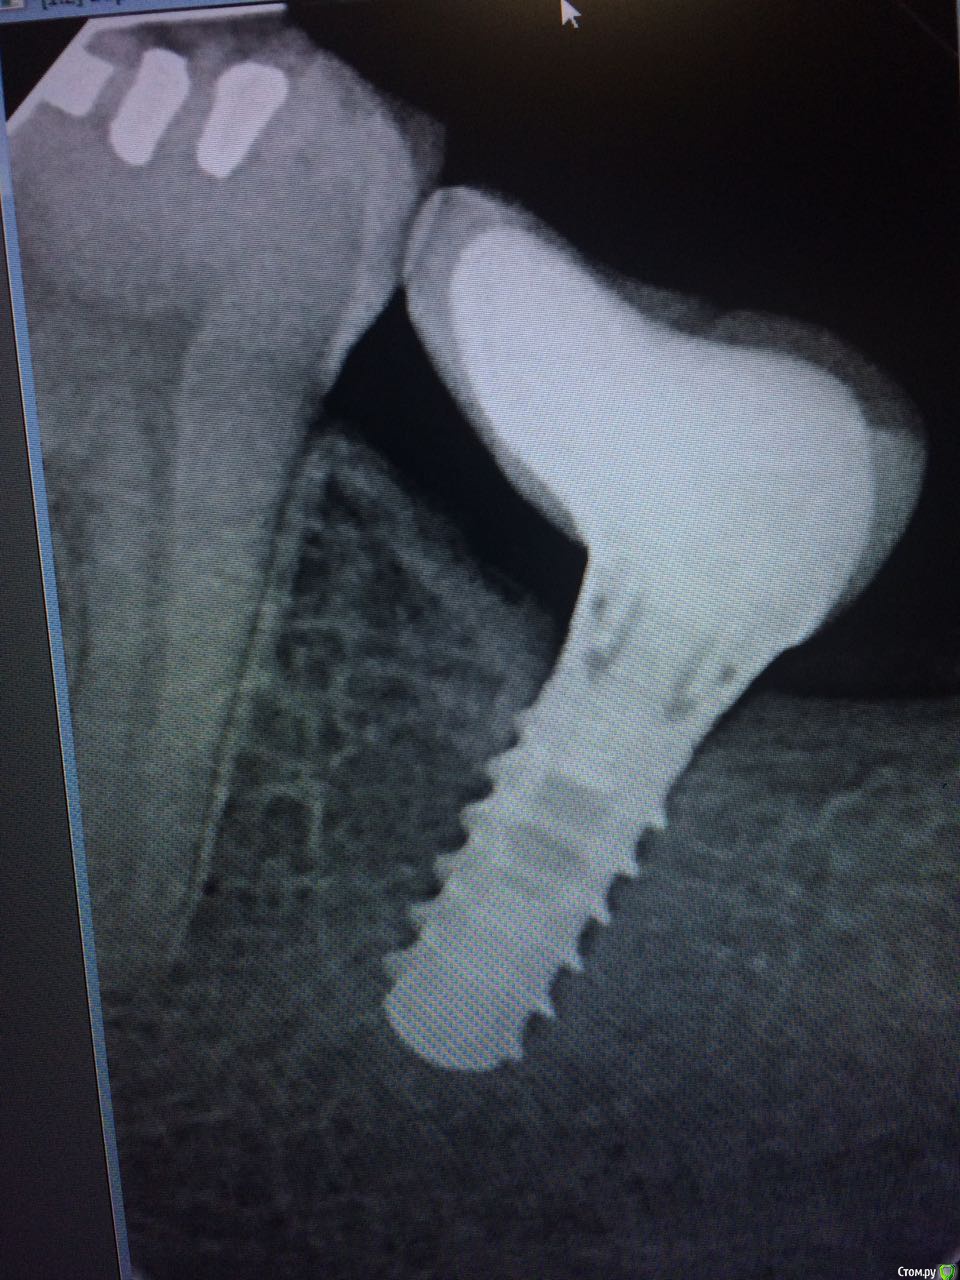

permico Опубликовано 23 августа, 2017 Поделиться Опубликовано 23 августа, 2017 (изменено) Добрый день.Примерно год назад во Франции мне были установлены 2 импланта на нижнюю челюсть взамен отсутствующих семерок (восьмерки были удалены еще раньше), т.е.37 и 47 зубов. Система Implant Direct (США), тип Swish plus, длина 10 мм. диаметр 5.7 и 4.1 мм. Врач уверил, что они являются репликой трансгингивальных Straumann Tissue Level с полированной шейкой и полностью совместимы. В общем, интегрировались они нормально, коронки он установил и я с ними проходил год без жалоб.Недавно сходил здесь в Москве к стоматологу, чтоб подкрутить винты на имплантах. Он все сделал и сказал, что нужно мне показаться хирургу-имплантологу так как они установлены скорее всего неправильно, забивается много пищи между коронками и десной (они сделаны с "балконом") и очень вероятно осложение в виде резорбции костной ткани. Сходил на консультацию к одному хирургу в Москве, он сказал, да действительно они неправильно установлены и им поможет только вынимайзинг с последующей установкой новых на то же место. Если сейчас не переустановлю, то через примерно пять лет их в любом случае придется вынимать, так как винт начнется оголяться, но уже кости будет меньше и будет труднее устанавливать новые.Хотел бы совета от специалистов на форуме, действительно ли они требуют удаления или можно сделать что-то другое. чтобы решить проблему.Прикладываю изображения (панорамный снимок после операции, недавние снимки имплантов, и фото их во рту, последние не очень хорошего качества, вечером могу попробовать переснять)Спасибо заранее, Борис Изменено 23 августа, 2017 пользователем permico Ссылка на комментарий

red_butler Опубликовано 23 августа, 2017 Поделиться Опубликовано 23 августа, 2017 показаний к удалению не увидел 9 Ссылка на комментарий

Art 7 Опубликовано 23 августа, 2017 Поделиться Опубликовано 23 августа, 2017 если хотите продлить жизнь имплантатам то надо выкрутить коронки, сделать пластику десны вокруг имплантатов и переделать коронки. это даст много лет жизни ималантатам 5 Ссылка на комментарий

Bier Опубликовано 23 августа, 2017 Поделиться Опубликовано 23 августа, 2017 понаблюдайте пока так. Чистите получше. Сейчас показаний к удалению нет. 1 Ссылка на комментарий